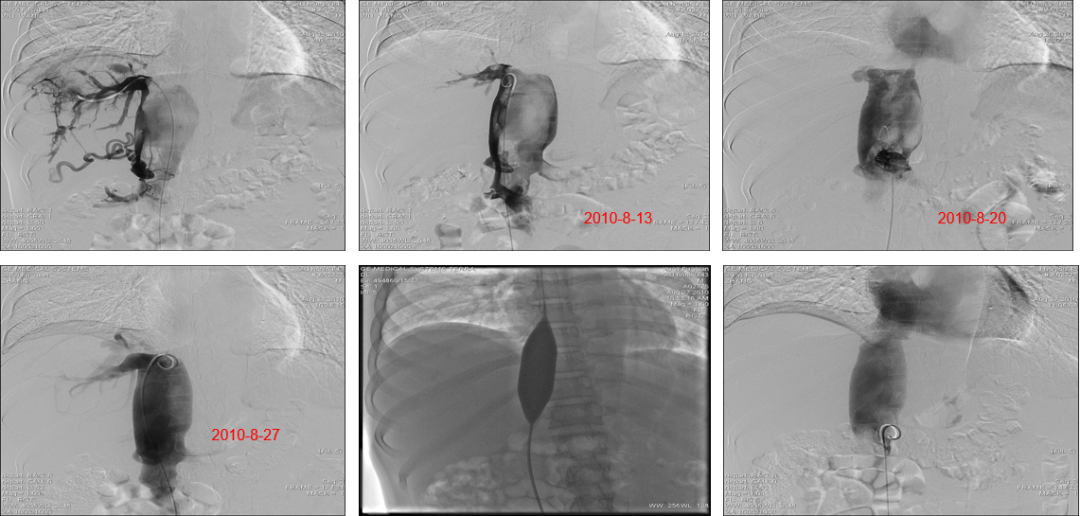

疑难病例:下腔静脉血栓形成的处理--留置导管溶栓

★ 再狭窄与反复再狭窄

收治BCS 4332例次

术中与围手术期死亡-- 4例 <1.‰

放弃治疗-- 5例

IVC+HV 全程闭塞未开通--61例

介入治疗成功率 -- 4262/4332 98.38%